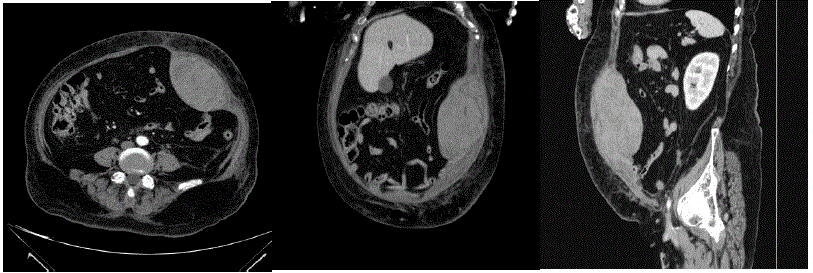

Realizada tomografia de abdome (imagens a seguir):

Qual é o melhor tratamento?